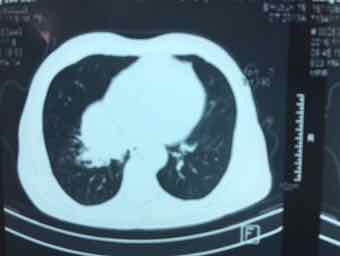

男,74岁,咳嗽咳痰3个月,无发热,无胸痛,无盗汗,无咳血。右肺占位性质待查?完善气管镜检查